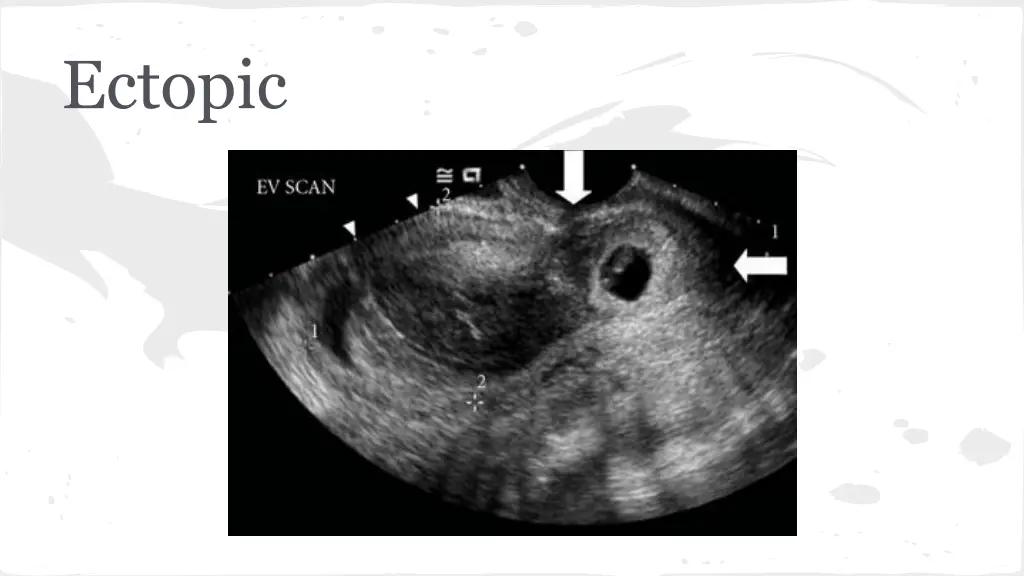

Ectopic Pregnancy-Likelihood Ratios CMT-4.9 Adnexal mass-2.4 Adnexal tenderness 1.9 Ultrasound-111 No IUP on US in pregant patient is ectopic until proven otherwise

Ectopic Pregnancy Symptoms Abdominal Pain Syncope Vaginal Bleeding Vomiting Exam Lower abdominal tenderness Adnexal TTP CMT Peritoneal Abdomen

Ectopic Pregnancy Labs Quant B-HCG, CBC, Coags, Type and Screen -very low B-HCG cannot rule out ectopic Management -STAT GYN consult -NPO -Medical vs Surgical Management